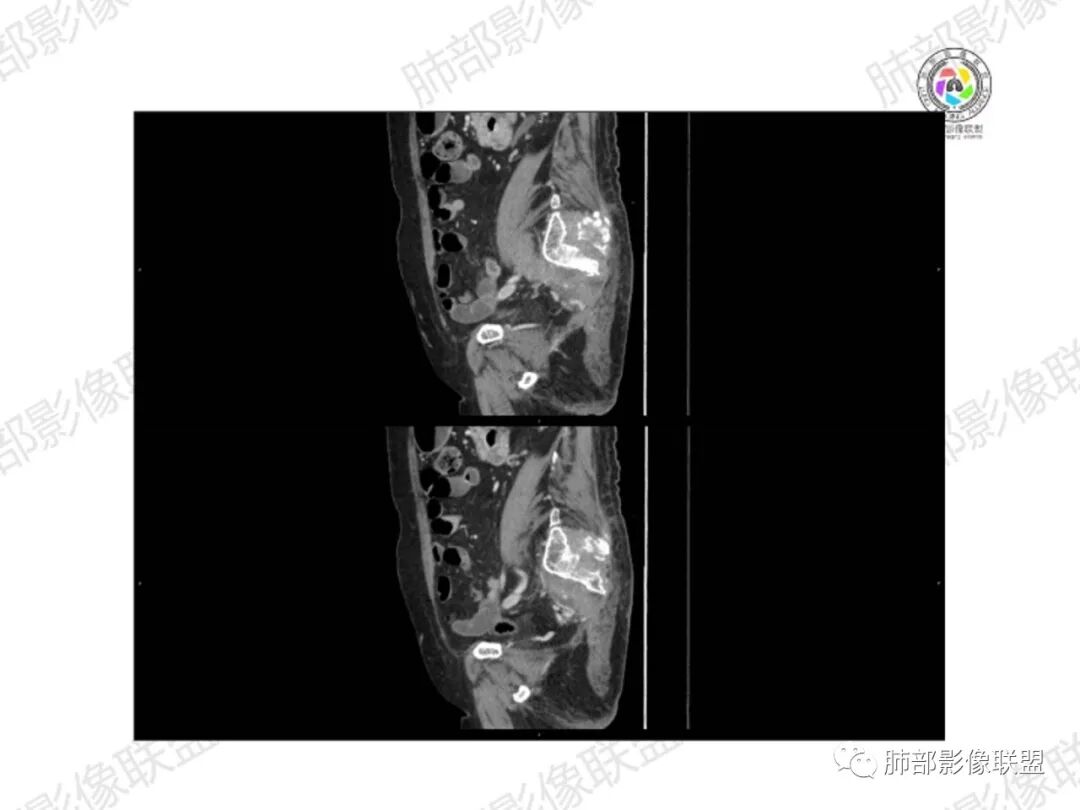

2.右髂骨轻度变形伴广泛骨质吸收破坏,边界不清且突破骨皮质。近中线区以溶骨性破坏为主,髂骨翼一侧则成骨性改变明显,骨表面见垂直骨针或花边样高密度瘤骨。

3.患骨多处皮质断裂,符合病理性骨折。注意折端可能会形成骨痂,但本例无论是形态还是部位都不符合骨痂。

4.患骨两旁(即盆骨内外)见边界不清的较大范围软组织快影,其间偶见骨化影。

1.边界不清的骨质吸收破坏,溶骨明显,骨皮质突破,软组织肿块,种种迹象表明其恶性无疑!

2.但注意这是有“成骨”的恶性骨肿瘤!我们知道老年患者的骨原发性恶性肿瘤“成骨”非常少见。少数转移瘤可为成骨型或混合型,女性患者如乳腺癌骨转移等。在男性,最典型的成骨转移是前列腺癌。

本例右侧髂骨具有较为典型的“骨肉瘤”影像学特征,有边界不清的吸收破坏、有新生骨、形成软组织肿块等等。